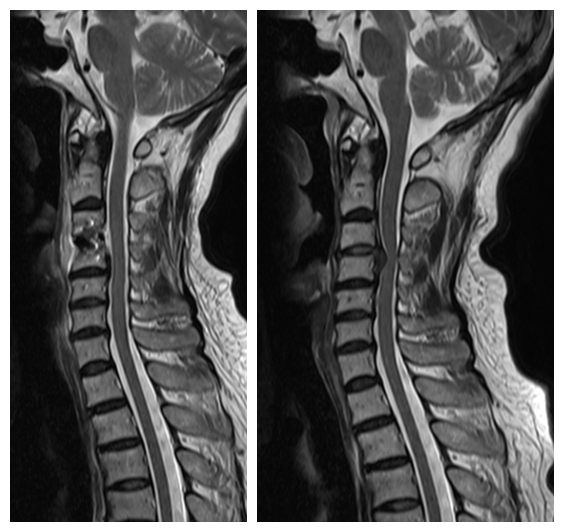

劉女士家屬知道惠州市第三人民醫(yī)院有個(gè)專治頸肩腰腿疼痛的科室,即來頸肩腰腿痛門診就診,入院后MRI示:頸3/4椎間盤變性并向后下脫出,頸3/4-6/7水平椎管狹窄及雙側(cè)神經(jīng)根受壓,以頸3/4水平狹窄為著。

術(shù)前MRI 和術(shù)后MRI

惠州市第三人民醫(yī)院骨科醫(yī)學(xué)中心主任武明鑫博士、頸肩腰腿痛科許球祥主任、孫進(jìn)主治醫(yī)師,詳細(xì)詢問劉女士病史、細(xì)致體格檢查、仔細(xì)閱讀輔助檢查,經(jīng)認(rèn)真分析討論,診斷為“脊髓型頸椎病”,認(rèn)為劉女士病情目前并不適合繼續(xù)保守治療,建議行骨科中心階梯療法中的開放手治療方案。